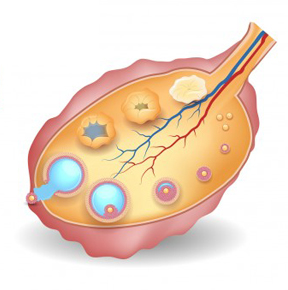

Le Docteur SENHAJI RHAZI Wassym, spécialiste en Gynécologie-Obstétrique et en Stérilité du couple, vous accueille dans son site d’information médicale destiné au grand public et dont le but est de vous éclairer sur toutes les questions que vous vous posez rattachées à sa spécialité.